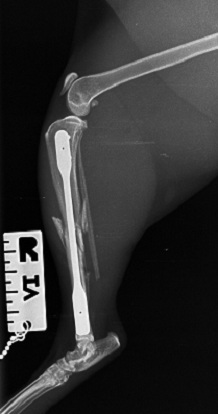

Feline tibia-fibula fracture, pre-op.

Feline tibia-fibular fracture, minimally invasive repair using a

LokRod plate of my design.

Feline tibia-fibular fracture, immediate post-op following LokRod repair.